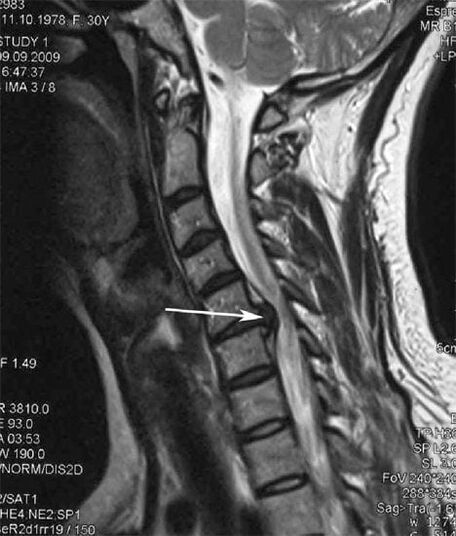

En las etapas iniciales, la osteocondrosis se detecta mediante resonancia magnética.. Posteriormente, la patología se puede diagnosticar mediante radiografía. En las radiografías de la columna cervical, se nota una disminución en la distancia entre las vértebras, cambios patológicos en las articulaciones facetarias y osteofitosis.